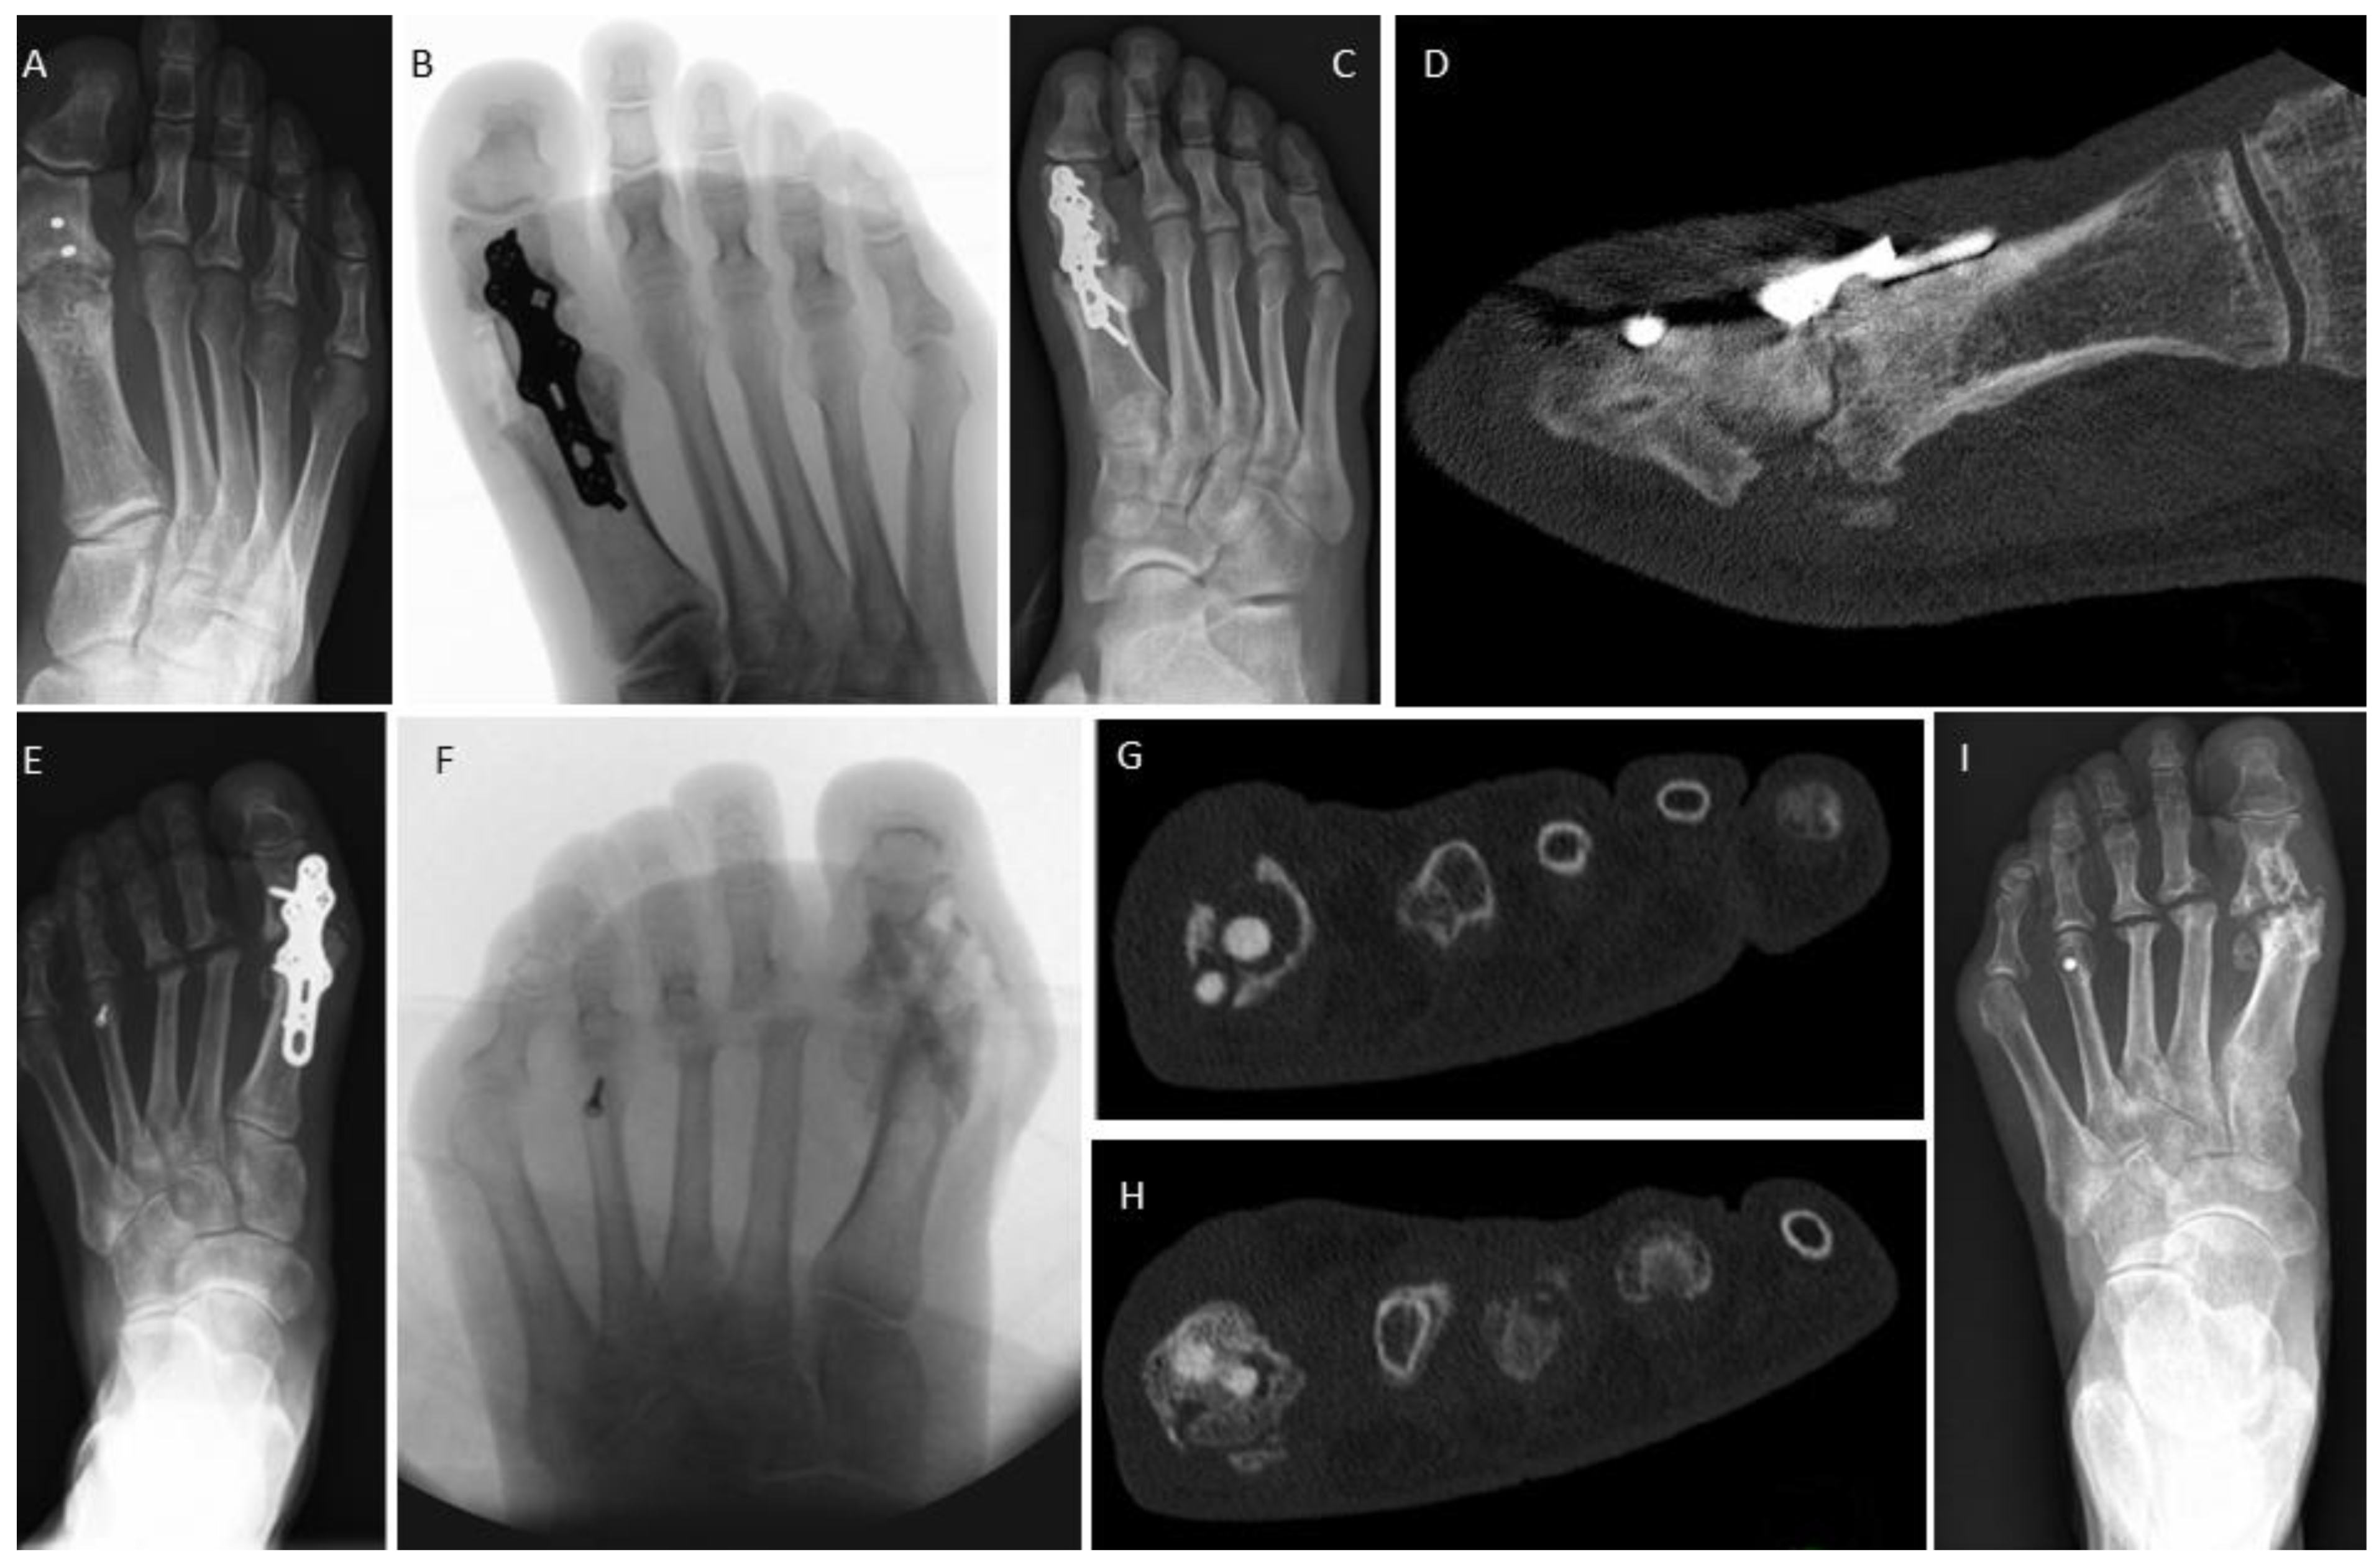

3.4. Examples for Bone Healing

3.6. Radiological Findings of Interest